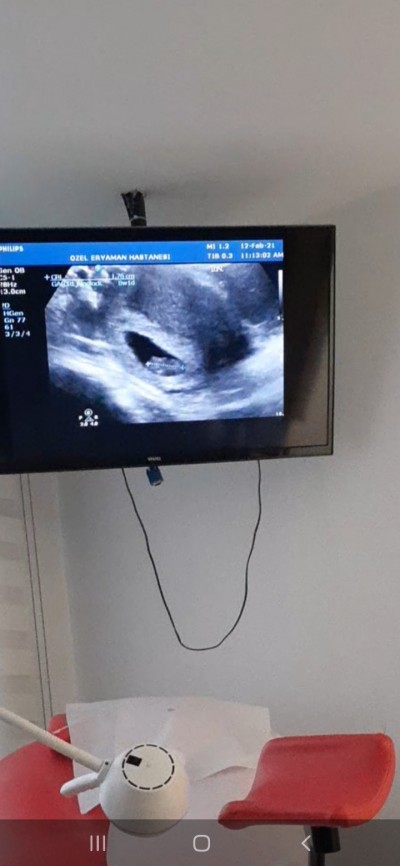

Merhaba ultrasonda 7+3dü kalp atışını duydum 1.20cm çıktı normal mi 8+1 olduk doktor 1 ay sonra çagırdı ve normal mı 2 gün geriden geliyor dedi doktorum

Gebelik haftası 8